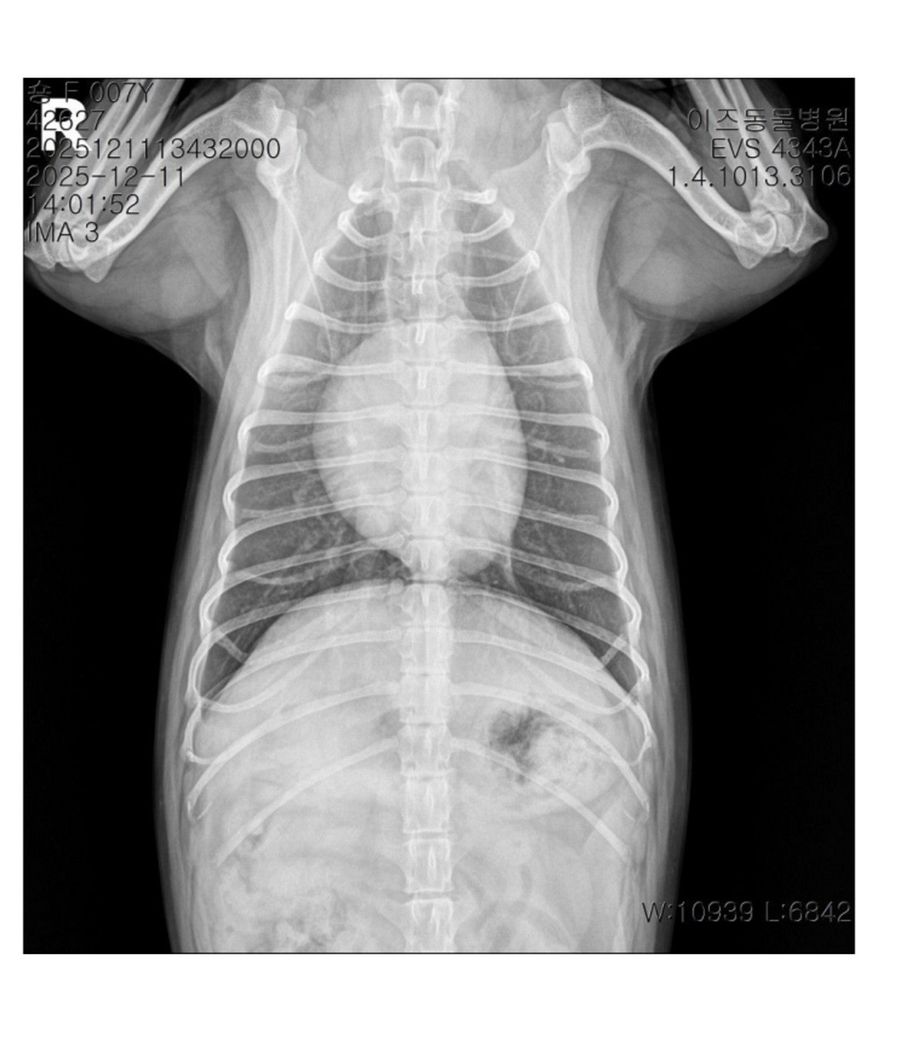

심장 모양 어떤가요 답변많이 해주세요

저의귀염둥이코자아기배찌통순통통모찌쫀득말랑찌순아기의 심장입니다.. 사진상 왼쪽 심장모양이 ㅠㅠ 나중에 심부전위험이있다고 하시더라고요 개순이 심장 관리팁좀..주세요ㅠ7년반 살았어요

제공하신 정보와 사진만으로는 심장의 정확한 상태나 심부전 위험을 평가할 수 없으며, 심장 관리에 대한 구체적인 조언은 진료하신 수의사에게 문의하시는 것이 가장 정확하고 안전합니다. 일반적으로 노령견의 심장 관리는 정기적인 동물병원 검진을 통해 심장 상태를 지속적으로 확인하고, 수의사의 지시에 따라 처방된 심장약을 꾸준히 복용시키며, 염분 섭취를 제한하는 심장 질환용 처방식을 급여하고, 과격한 운동 대신 가벼운 산책을 하는 것이 중요합니다.